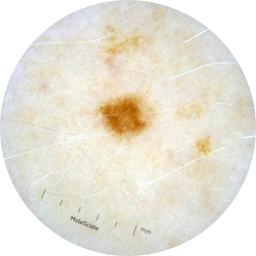

ISIC_2261268

acquisition_day 307

age_approx 50

anatom_site_1 Trunk

anatom_site_2 Posterior trunk

anatom_site_general posterior torso

diagnosis_1 Benign

diagnosis_confirm_type single image expert consensus

image_type dermoscopic